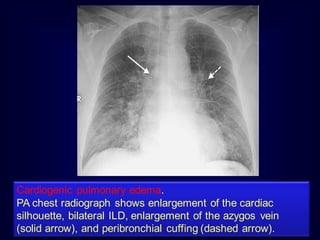

Cardiogenic pulmonary edema.

PA chest radiograph shows enlargement of the cardiac

silhouette, bilateral ILD, enlargement of the azygos vein

(solid arrow), and peribronchial cuffing (dashed arrow).